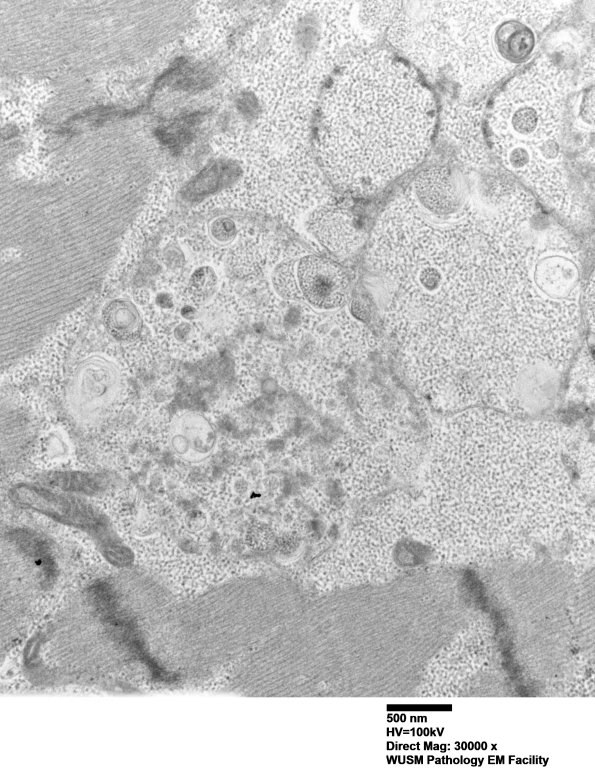

Washington University Experience | METABOLIC | Pompe Disease | 5D12 Muscle (Case 5) EM024 - Copy

5D12 Muscle (Case 5) EM024 - Copy

The cytosomes here are a mixture of the previous elements with both free and membrane bound glycogen. (electron micrographs)